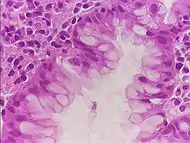

Гистологический метод

Первым методом, который стали использовать для диагностики геликобактерной инфекции, является гистологический метод. Материалом исследования являются клетки тканей, полученных с помощью биопсии, производимой во время эндоскопического обследования желудка и двенадцатиперстной кишки. Специфичность гистологического метода может достигать 100%, а чувствительность — 91-93%, ввиду того, что бактерии неравномерно распределены по слизистой оболочке желудка: взятие производится из мест с максимально выраженной гиперемией и отёком, при этом взятие из дна язв и эрозий, а также из их краев, является ошибкой, поскольку в них нет эпителиальных клеток, необходимых для колонизации бактерий. Кроме того, приём антибиотиков и ингибиторов протонной помпы может трансформировать бактерии из спиралевидной формы в кокковую, которую невозможно выявить с помощью обычной микроскопии.[52]